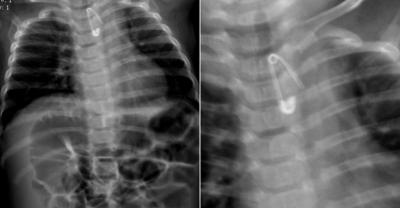

Lekarka z SOR zrezygnowała z pracy

Lekarska ze Szpitalnego Oddziału Ratunkowego w Krotoszynie, która miesiąc temu odesłała do Ostrowa Wielkopolskiego 6-miesięczne dziecko z agrafką w przełyku – zrezygnowała z pracy.

Lekarska dostała upomnienie

Dyrekcja szpitala bije się w pierś. Przyznaje, że zachowanie lekarki , która odesłała rodziców z 6-miesięcznym dzieckiem do lecznicy do Ostrowa Wlkp. – nie zapewniając transportu – było niewłaściwe. Szef do spraw medycznych – Mieczysław Pełko – karze lekarkę pisemnym upomnieniem.